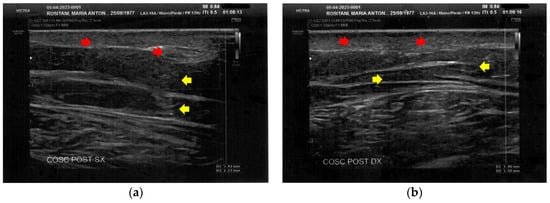

3.1. Basal Imaging Evaluations

3.2. Imaging Evaluations After the Treatment